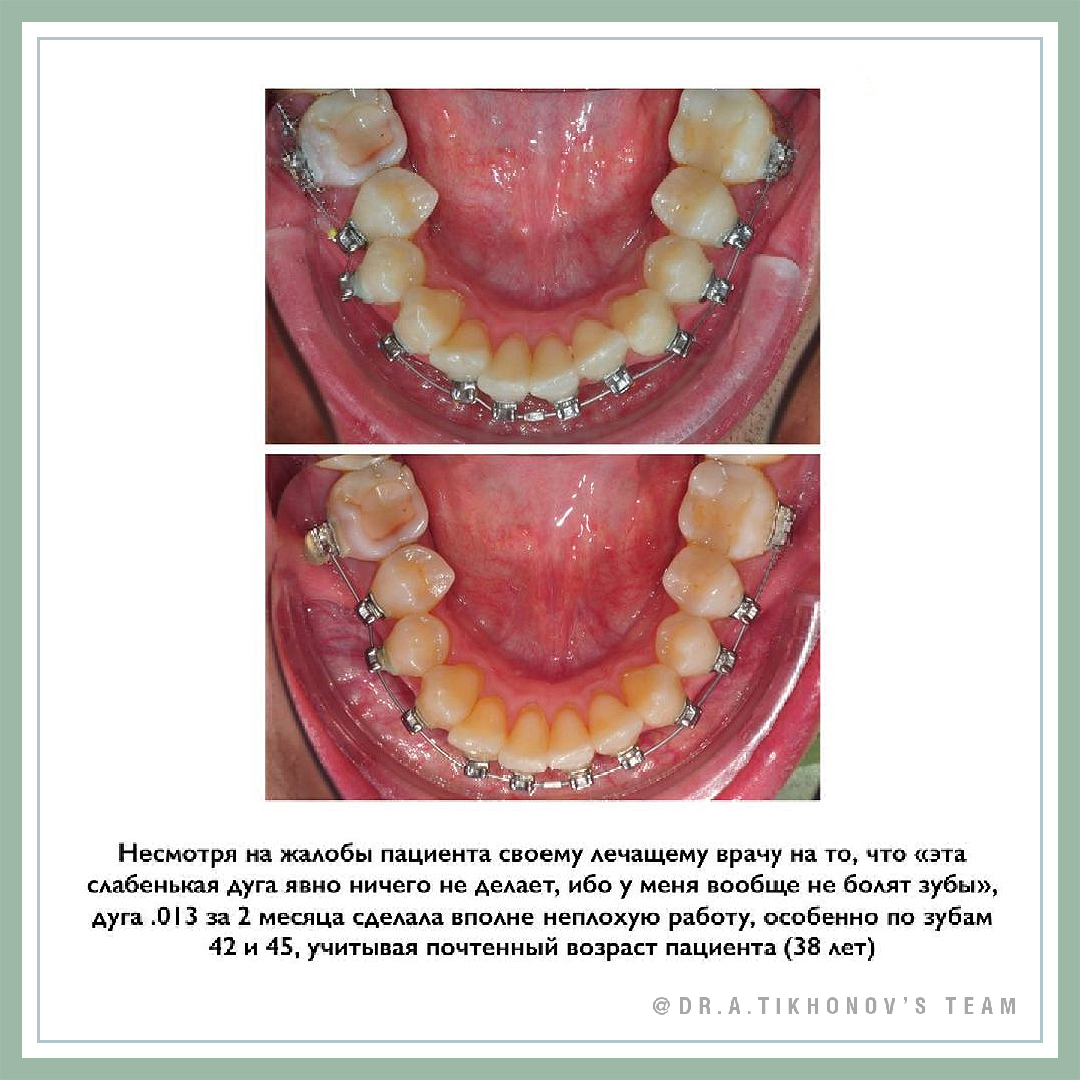

- При использовании слабых сил, и правда, может практически не быть ощущений при перемещении зубов. Пациент лично ощущал это на этапе первых дуг, а также при движении 27 зуба на место 26 никель-титановой пружиной.

- Без разобщения можно наслаждаться привычным смыканием (ну, если оно было в принципе до лечения). Если зубы высокие, то можно поставить нижние брекеты поближе к десне, чтобы в них не кусали верхние. Это легко спланировать при непрямой фиксации. У этого пациента я, кстати, лично ставил брекеты на модель!